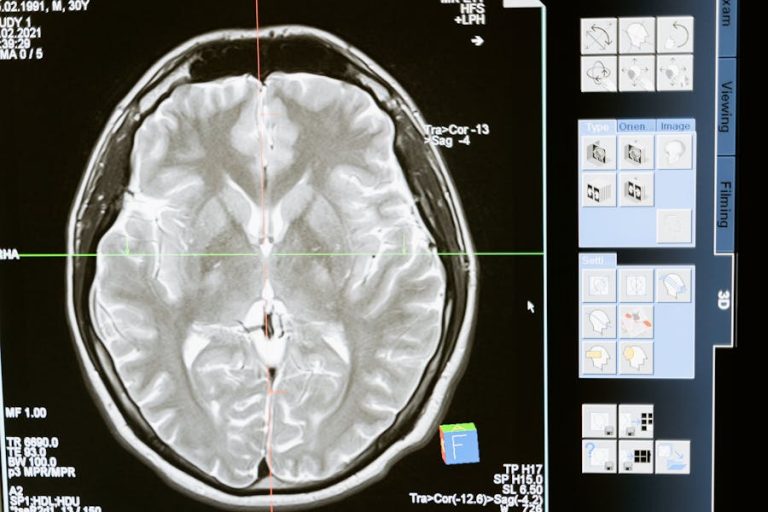

O que é o sangramento intracraniano?

Um sangramento intracraniano é uma hemorragia que ocorre dentro do crânio do indivíduo podendo causar fortes cefaléias, náuseas, crises epilépticas, vômitos, falta de equilíbrio, letargia, desmaios e até mesmo déficits neurológicos.

A depender da proporção da hemorragia, o problema pode ser fatal em poucos dias podendo também gerar sequelas após a recuperação por danificar as células cerebrais